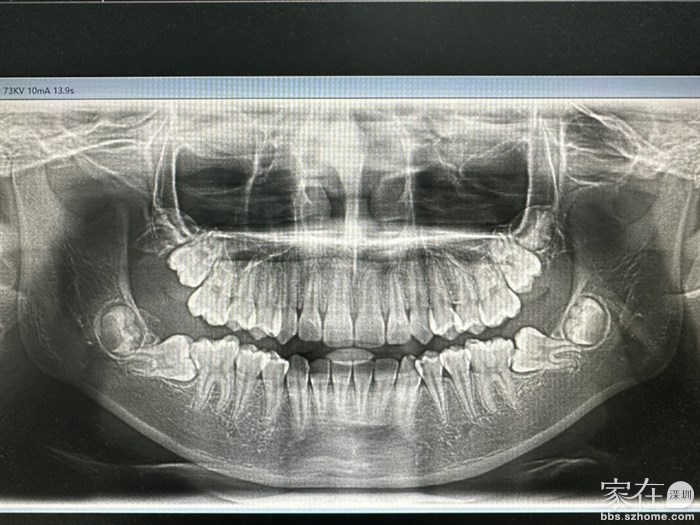

引用牙牙天使的发言:方案1:把下颌两颗7号牙拔除,让后面的智齿随便长,但有个风险对颌(上颌7号牙)全伸长

方案2:把下颌两颗7号牙通过矫正可以扶正。具体情况还是需要拍CT出方案,看看哪种方案合适

二、如果拔掉七号牙,有很大一个空缺,智齿慢慢会往前移动与磨牙挨上吗?引用3楼牙牙天使的发言:方案1:把下颌两颗7号牙拔除,让后面的智齿随便长,但有个风险对颌(上颌7号牙)全伸长